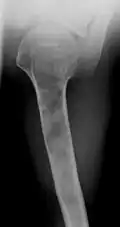

X-ray showing enchondromas localized in the humerus of a 37-year-old patient affected with Ollier disease